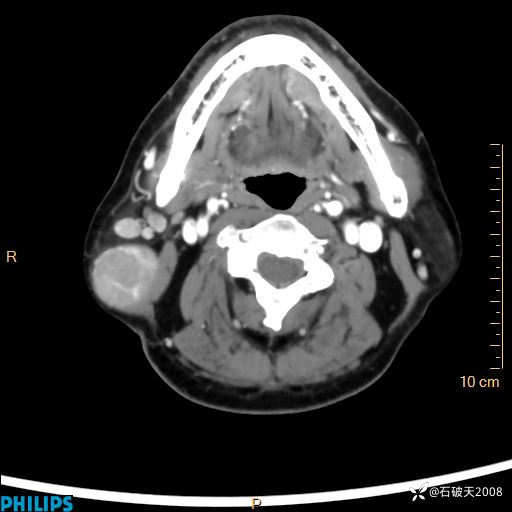

静脉期